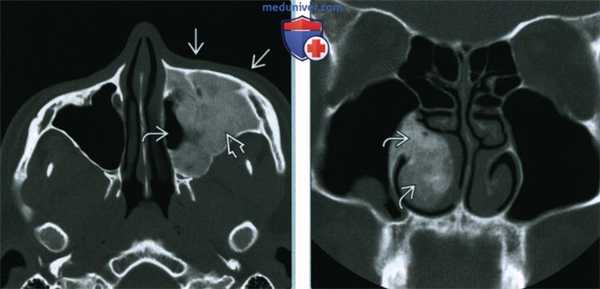

(Слева) При корональной «костной» КТ определяется экстенсивная фиброзная дисплазия орбит, петушиного гребня, решетчатой кости, среднего носового хода справа. Носовая перегородка отклонена влево.

(Справа) При аксиальной MPT Т2 в зоне фиброзной дисплазии определяется характерный выраженный гипоинтенсивный сигнал. Эти изменения типичны, когда наблюдаются совместно с «матовым стеклом» на КТ, и более диагностически значимы, чем гиперинтенсивные на Т2 очаги.